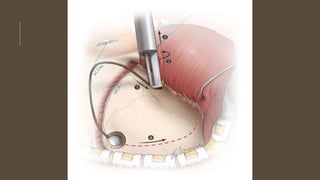

• SPECIFIC MANAGEMENT

• Clipping

• Pterional approach

• Bifrontal approach

• Coilling